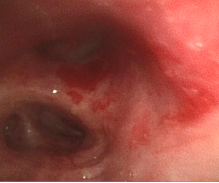

支气管镜:

隆突

左肺下叶开口

右中间支气管

10-20患者出现发热,支气管镜下:左肺下叶开口大量脓性分泌物伴气道痉挛

该患者为马尔尼菲篮状菌的重度感染,马尔尼菲篮状菌病为少见疾病。马尔尼菲篮状菌病(Talaromycosis,TSM)是由马尔尼菲篮状菌引起的侵袭性真菌病。该菌主要侵犯单核-巨噬细胞网状内皮系统,故而容易在淋巴结、肝、脾、肺、皮肤等发生病变。流行病学显示,90%以上病例出现在免疫力受损患者,尤其是艾滋病患者的免疫功能进一步下降,加剧了马尔尼菲篮状菌播散。TSM的影像学表现多种多样,包括大片实变、结节、磨玻璃改变、粟粒样病变、肺门或纵隔淋巴结肿大、胸腔积液、空洞、坏死,以及细菌性肺脓肿,内壁光滑,甚至有气液平面。气管镜下为气道内壁光滑的凸起结节,伪膜、溃疡等少见。